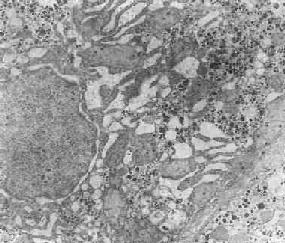

在由各种原因引起的细胞变性和坏死过程中,粗面内质网的池一般出现扩张,较轻的和局限性的扩张只有在电镜下才能窥见,重度扩张时则在光学显微镜下可表现为空泡形成,电镜下有时可见其中含有中等电子密度的絮状物。在较强的扩张时,粗面内质网同时互相离散,膜上的颗粒呈不同程度的脱失。进而内质网本身可断裂成大小不等的片段和大小泡(图1-6)。这些改变大多见于细胞水肿时,故病变不仅见于内质网,也同时累及Golgi器、线粒体和胞浆基质,有时甚至还累及溶解体。

肝细胞粗面内质网扩张

图1-6肝细胞粗面内质网扩张